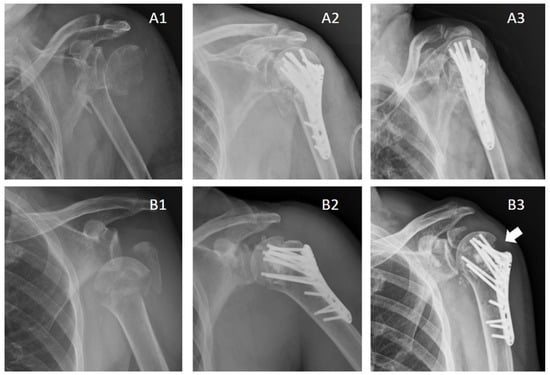

3.2. Our Experiences